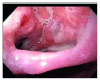

Bronchoesophageal Fistula due to Esophageal Tuberculosis

This is a case report regarding a patient who presented with 6 months of dysphagia and subsequent 40-pound weight loss. The patient underwent imaging, suggestive of pulmonary TB. Further workup of his dysphagia with esophagogastroduodenoscopy and bronchoscopy revealed two bronchoesophageal fistulas. Tuberculosis is an important differential diagnosis of prolonged dysphagia in immunocompetent patients.